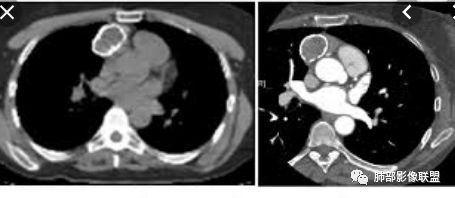

王兆宇老师:畸胎瘤总有油脂物质密度,块状钙化少见,环状钙化多见,头结节骨化多见,畸胎瘤钙化不在中间。

纵隔或胸膜伴钙化疾病谱(吴婧):A:异位甲状腺——最常见,甲状腺癌非常容易钙化,一般与甲状腺相连,平扫因为摄碘,CT值很高,增强后则明显增高。B:畸胎瘤——脂肪、牙齿密度可识别。一般多发年轻30岁左右,钙化特点为块状钙化少见,环状钙化多见,钙化不在中间(偏心钙化)。很少强化或轻度强化                            (王兆宇老师)C:CD透明细胞型——一般钙化为条状钙化,病灶形态通常为圆形、光滑、规则、全实性,不软所以不会见缝就钻,也不会坏死,强化非常高。D:胸腺瘤——一般30岁以后,容易钙化为A、AB、B1型,B2型以后钙化少见。钙化特点为大块状钙化、中间钙化。E:SFT——钙化会沿着胸膜的长轴生长。

有脂肪,有钙化,钙化为条状,不是块状,偏心

随机翻阅以上20个病例,都是畸胎瘤伴钙化的,发现只有2例钙化是团块状,且都是偏心的。其余18例钙化都是颗粒状、条状和包膜弧形钙化。有9例是多发钙化,且比较散,不聚集。总之,比较少会出现单发中心性的团块钙化。20例均没有,虽然样本少,但是均符合王兆宇老师说的规律。

第一种是弧形钙化,是囊性畸胎瘤的弧形钙化。

第二种条状钙化可能是血管钙化,脉管钙化。

第三种团块状或一颗颗的可能是牙齿,一般都不会太大,而且比较散在。

胸腺瘤钙化

大部分钙化还是包膜钙化和条状,结节状钙化,团块状钙化也比较少。位置中央,周围都可以。